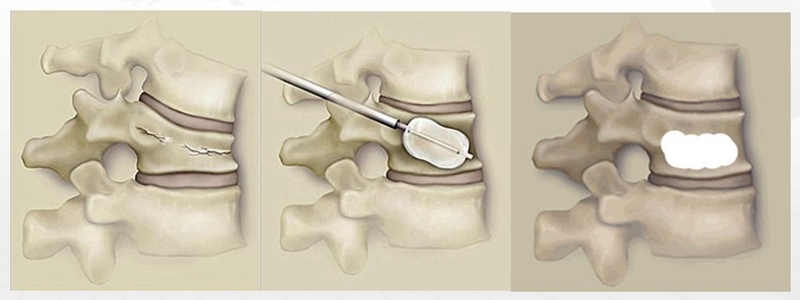

VBS的优势在术中可使球囊撑开的椎体高度得以有效维持,避免了PKP术中球囊撑开椎体撤出后,椎体高度又部分丢失的情况;在灌注骨水泥时,与PKP同样可减少骨水泥渗漏风险。缺点在于金属支架放置位置要求比较高,如果放置不当或骨水泥不能完全填充支架内部,术后影响止疼效果,同时增加了伤椎再骨折的风险。

PCKP的优势在于术中操作安全、便捷、骨水泥弥散好,渗漏率低。术中穿刺过程中穿刺针以更小的穿刺角度进入椎体内,通过弯角骨钻开腔越过椎体中线,增加了穿刺安全区间,减少了术中医源性穿刺损伤的风险;同时通过弯角球囊的独特设计,可以在椎体中部造成弧形空腔,引导骨水泥在灌注过程中从穿刺对侧开始弥散,沿球囊撑开的弧形空腔充分灌注,达到单侧穿刺、双侧弥散的效果,有效降低了骨水泥渗漏风险。